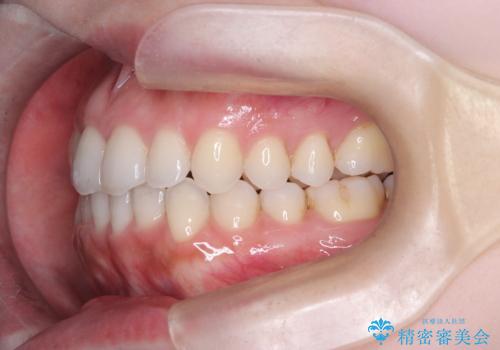

- 前歯の凸凹を主訴に来院された患者様です

骨格性の下顎前突傾向もあったため、臼歯関係の遠心移動も行うことで綺麗な仕上がりで矯正を終了することができました。

遠心移動を行うことで期間はかかりましたが、良い状態で仕上がっています。